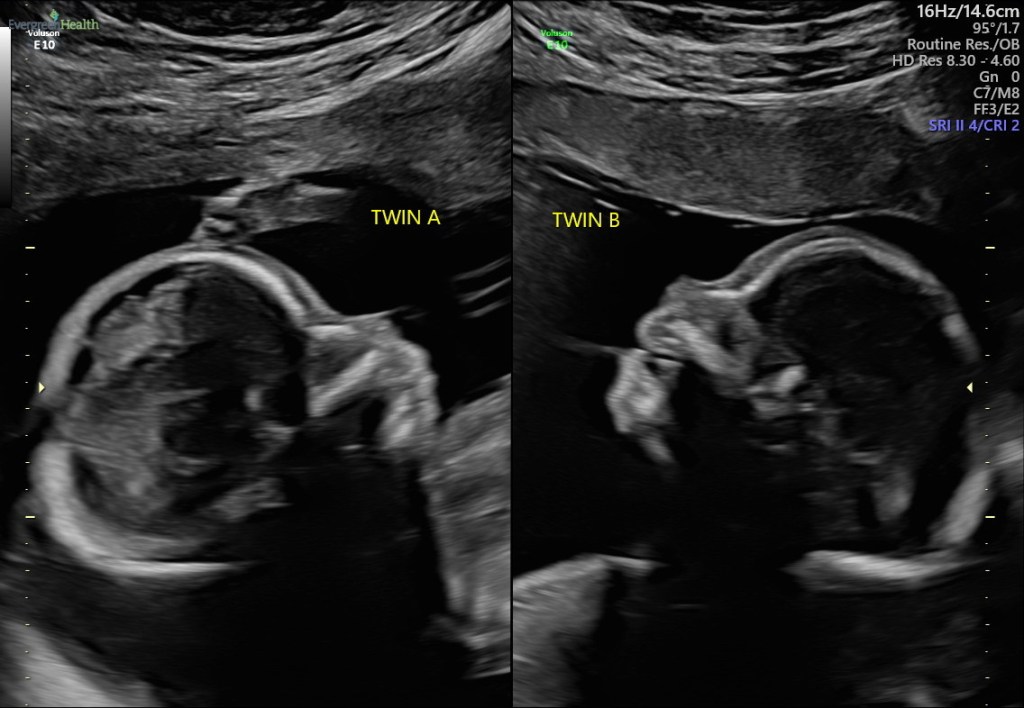

02/23/2021: Tues 23w3d |Growth is trending upward! Babies look good!! Really great news for them!!!

Both of our babies experienced growth in the last two weeks. Baby B or Daniel is almost in the 80th percentile, and baby A , or Joshua has gone from fifth back up to the 10th percentile!!! Since we were told to expect it to continue to drop until delivery, baby A or Joshua’ s upward growth has delighted us!!!